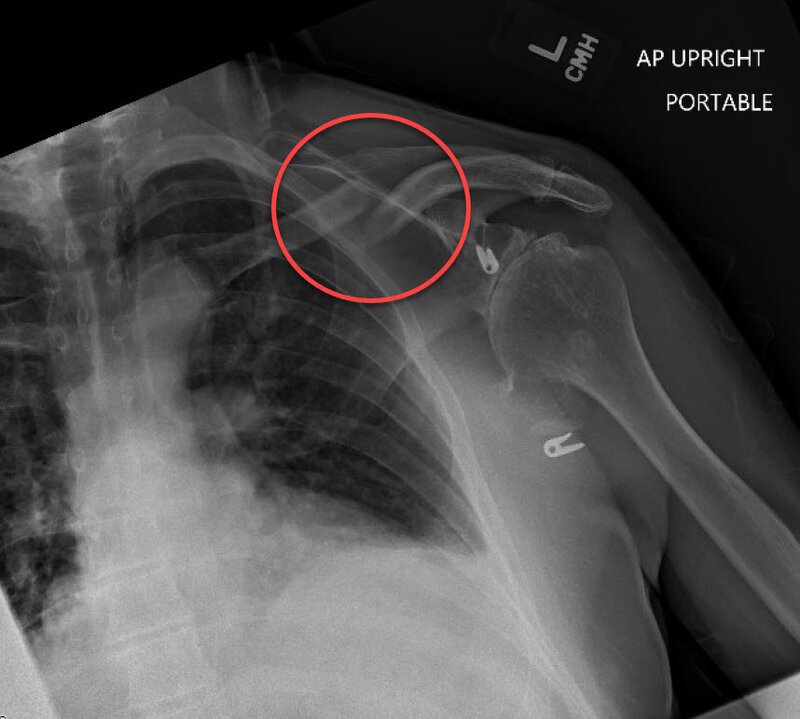

X-ray immediately following my accident 8/31:

X-ray immediately following my accident 8/31: